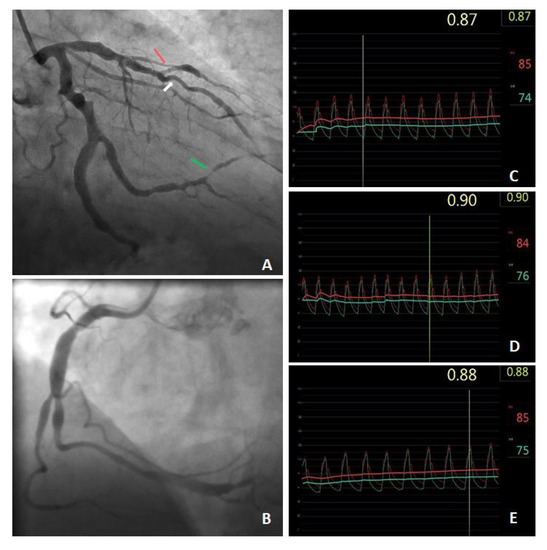

Fractional Flow Reserve in the Diagnosis of Ischemic Heart Disease in a Patient with Coronary Artery Ectasia